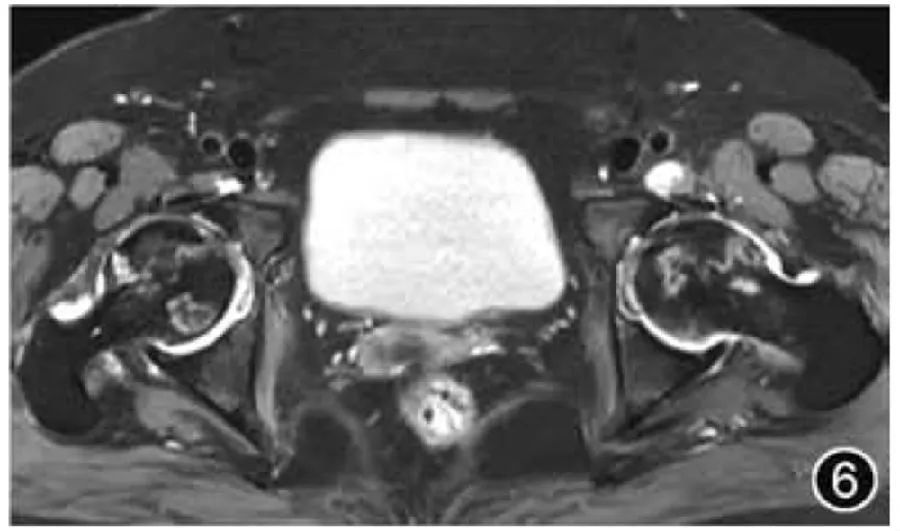

5. Аваскулярный некроз головки бедренной кости. Поскольку аваскулярный некроз головки бедренной кости часто возникает двусторонне, при визуализационном исследовании следует выбирать МРТ обоих тазобедренных суставов, при этом особое внимание следует уделять оценке симметрии двусторонних тазобедренных суставов. Типичный аваскулярный некроз головки бедренной кости проявляется в виде субхондрального поражения в форме полумесяца с окружающим его краем со слабым сигналом на МРТ и характерным «признаком двойной линии» на Т2-ВИ (рис. 6). Необходимо описать локализацию и размер остеонекроза, предполагаемый процент пораженного объема головки бедренной кости (<15%, от 15% до 30%, >30%) и стадию поражения. Поскольку коллапс головки бедренной кости представляет собой более запущенное заболевание и необратимое повреждение, следует ли описывать коллапс головки бедренной кости (менее 2 мм – легкий, ≥2 мм – умеренный или тяжелый), а также наличие вторичного ОА бедра и фрагментации головки бедренной кости. должно быть описано. Основные сигналы остеонекроза можно использовать для оценки стадии. Сигнал жира указывает на поражение в сверхострой фазе или фазе заживления, сигнал о отеке костного мозга указывает на поражение в острой или подострой фазе, а сигнал остеосклероза указывает на поражение в хронической фазе.

Рисунок 6. МРТ-изображение аваскулярного некроза головки бедренной кости. На поперечном сечении T2WI видны две полосы высокого сигнала с обеих сторон головки бедренной кости, высокие внутри и низкие снаружи, что представляет собой признак двойной линии.